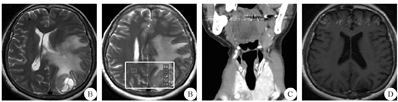

患者2 女性,61岁,因"右下肢乏力2个月余"于2016年6月2日入院。患者于2个月前自觉右下肢乏力伴言语欠流利,无头晕、头痛,无恶心、呕吐,无视物模糊,无抽搐。自起病来,患者精神尚可,二便无异常。既往有甲状腺肿大病史30余年,未行治疗。体检:神清,一般情况良好,KPS评分100分。甲状腺检查示左侧甲状腺二度肿大,左、右侧甲状腺均可触及结节,边界清楚,质地较韧,表面光滑,可随吞咽上下移动。神经系统检查:左侧肢体肌力正常,右下肢肌力4+级,右上肢正常,其他无异常。实验室检查无异常,胸部CT、心脏、肝胆胰脾、泌尿生殖系彩超均未见明显异常。甲状腺彩超示:双侧甲状腺内多个低回声光团,右侧甲状腺内最大直径约为2 cm,考虑甲状腺肿瘤。头颅MRI示:左枕叶一个类圆形肿物,呈稍长T2信号,边界清楚,左枕顶叶大片脑水肿灶,左侧脑室受压变形,中线右偏1.5 cm;增强后肿物明显强化,基底与硬膜相连(图3A)。磁共振波谱(MRS)示:N-乙酰门冬氨酸(NAA)/胆碱(Ch)、NAA/肌酸(Cr)值降低,Cr峰及NAA峰降低、Ch峰增高(图3B),考虑为脑膜瘤或血管周细胞瘤。颈部CT示:甲状腺增大,左右叶及峡部内多个大小不等、混杂密度肿块,边界欠清,左侧甲状腺最大肿块直径为1.8 cm×2.1 cm×2.2 cm,右侧最大直径为3.3 cm×2.7 cm×2.8 cm;颈部Ⅰ~Ⅳ区均可见数枚小淋巴结影,较大者约0.6 cm×0.5 cm(图3C),考虑甲状腺肿瘤。2016年6月11日行左侧枕叶肿瘤切除术,术中见肿瘤位于蛛网膜下腔,与硬脑膜无黏连,呈紫红色,边界清楚,有薄层包膜,质地偏软,血供丰富,与脑表软膜关系密切,将肿瘤与正常脑组织分离后完整切除。术后患者恢复良好,MRI复查示:肿瘤已完整切除(图3D)。术后病理结果:HE染色为腺癌,部分腺腔内见红染胶质样物(图4A)。免疫组化染色:CK19(部分+),TTF-1(90%+),G-3(+),甲状腺球蛋白(+),P53(-),Ki-67(5%+)(图4B)。诊断为转移性甲状腺癌。2016年6月28日患者在本院行双侧甲状腺全切术+峡部锥状叶切除术,术后病理结果:甲状腺滤泡癌。术后转核医学科行131I、甲状腺激素替代治疗。随访4年,未见肿瘤复发。

A:术前轴位T2 FLAIR增强;B:术前MRS;C:术前冠状位颈部CT;D:术后轴位T1 FLAIR增强;FLAIR:液体衰减反转恢复序列;MRS:磁共振波谱